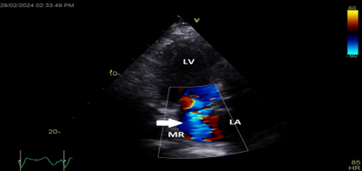

Color Doppler mapping of the mitral valve showed severe mitral regurgitation (MR) (Figure 4).

Figure 4: Apical long axis view still frame showing severe mitral regurgitation (white arrow)

LA=left atrium; LV=left ventricle; MR=mitral regurgitation